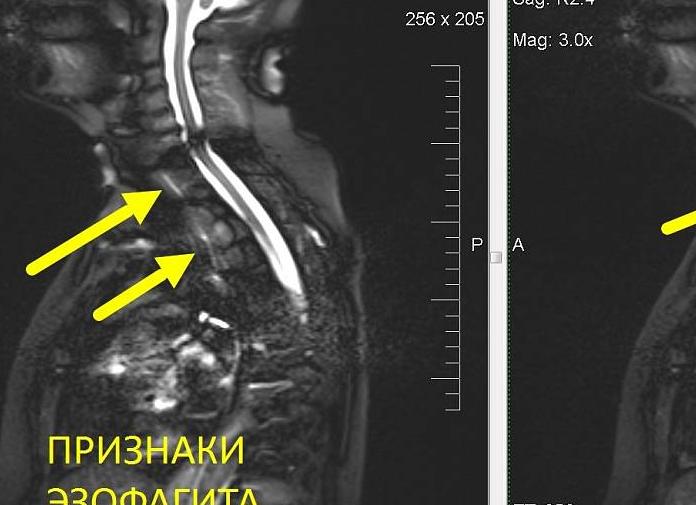

5. Эзофагит.

Это воспаление слизистой оболочки пищевода, вызванное инфекцией (чаще всего кандидой или герпесом) или механическим раздражением, например, из-за частой рвоты. При эзофагите, кроме таких распространенных симптомов, как изжога, неприятный привкус во рту и запах из него, тошнота, пациент жалуется на то, что ему тяжело и больно глотать. У него есть ощущение, будто пища застревает в пищеводе, при этом его могут беспокоить боли в груди, отдающие в спину.

- Оценивает степень утолщения стенок органа. Необходимо при гастритах или эзофагитах. Воспаление слизистой пищевода и желудка может сопровождаться утолщением стенок. Поэтому проведение МРТ целесообразно для оценки именно диаметра утолщения. Такие сведения помогут скорректировать проводимую терапию.

МРТ пищевода назначается при эзофагите, диафрагмальной грыже, подозрении на опухоль